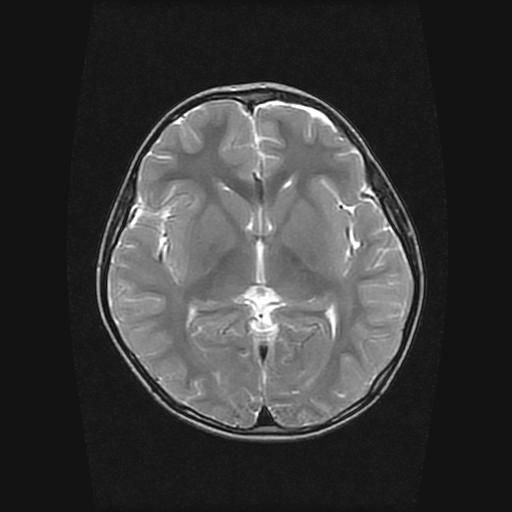

6岁小儿,左侧视神经瘤术后。现左侧视力减退。